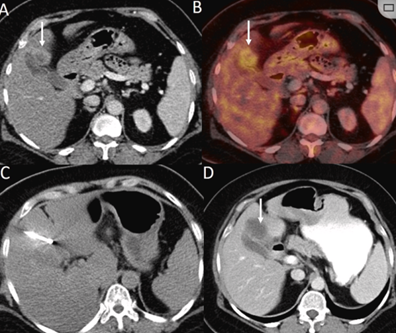

79 歲男性,肝轉移(結直腸癌)腫瘤的完全消融病例

( a ) 軸向 MRI 和 ( b ) 軸向 CT 顯示肝S8段有一個16mm的病灶,鄰近肝緣。( c )冷凍消融期間CT顯示放置了2個冷凍探針,低密度冰球包圍病灶。(d)術后1個月隨訪 CT顯示冰球對應的壞死區(qū)域,未見復發(fā)。(e)術后6個月的CT,壞死區(qū)域縮小,未見復發(fā)。(f)與基線影像(g)相比,12個月后的FDG-PET/CT顯示未見FDG攝取。

(a)軸向CT顯示病變位置毗鄰心臟和上腔靜脈(黑色箭頭)。1個月后的軸向(e)和冠狀位(f)增強CT掃描顯示低密度區(qū)域,由于肉芽組織反應引起的邊緣增強。